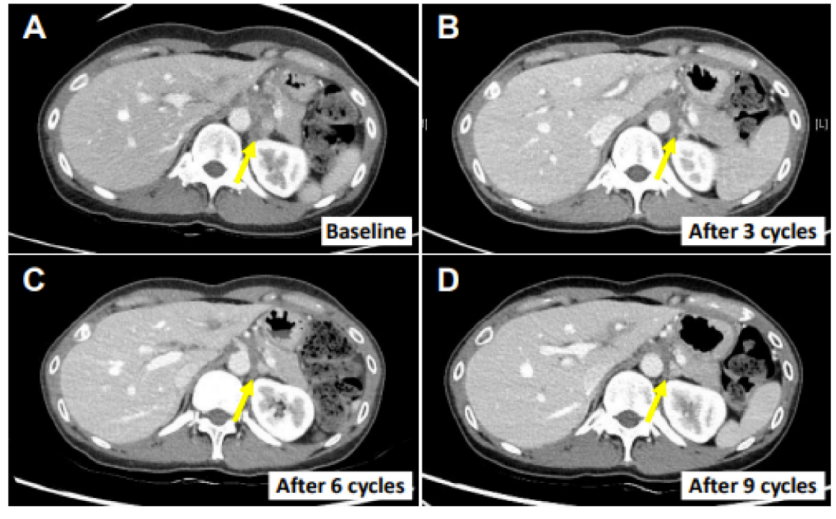

近年来,免疫细胞治疗已经成为肿瘤临床上热门领域,且相关治疗产品获批上市。在《International Journal of Molecular Sciences》中总结与归纳了NK细胞和癌症免疫治疗的发展概况,旨在帮助人们了解NK细胞在癌症治疗领域的应用与潜力,用自己的NK细胞来对抗肿瘤,已经在临床得以应用。 胆道癌:转移淋巴结减少了82.3% 来自韩国的科研团队在《CANCERS》期刊上发表了有关晚期胆道癌的联合用药研究结果,利用NK细胞与常见免疫抑制剂帕博利珠单抗联合治疗化疗难治性胆道癌患者的安全性和有效性。[1]

图片显示为患者 E0107 的左肾下淋巴结的变化情况,患者的癌症消退 根据研究中的临床试验表明:回输NK免疫细胞后,胆囊癌转移淋巴结减少了82.3%。证实NK细胞是免疫系统守护机体健康,消灭肿瘤细胞的强大武器,有望成为晚期患者的“最后防线”,具有重要的医学价值。 非小细胞肺癌:生存期显著延长